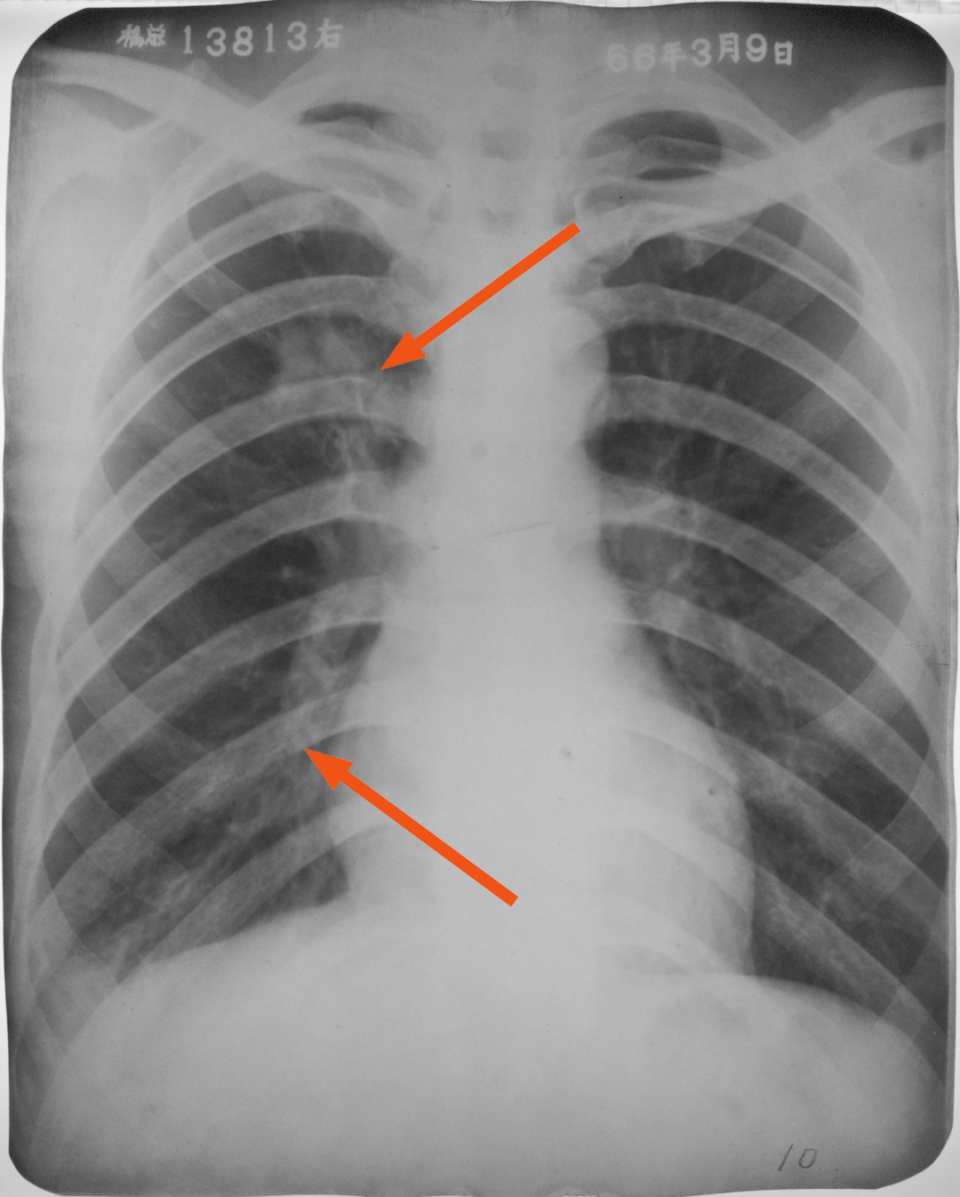

右上、下肺支原体肺炎

图片

胸部正位片示:右上、下肺野肺纹理增粗,可见斑片状阴影,密度较淡,局部呈扇形自肺门部发出(箭头所指)